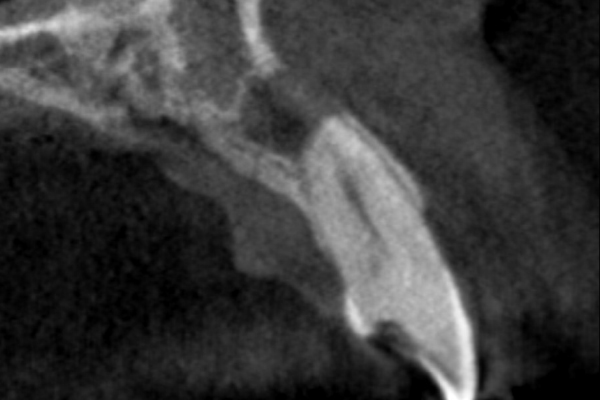

【札幌駅前】外科的歯内療法 (歯根端切除術)

50代男性の前歯部の症例

- 主訴

- 「時々歯茎が腫れる」とのことでご来院されました。数週間前から症状があり、他の医院では「抜歯の可能性がある」と言われ、不安に感じていらっしゃいました。

- 期間

- 治療回数2回、レントゲン写真で治癒を確認できるまでの期間6ヶ月

- ●外科的歯内療法(歯根端切除術)(前歯)132,000円(税込)

- 治療内容

- 1.麻酔

手術する部分に局所麻酔を行いますので、治療中に痛みを感じることはありません。

2.歯肉の切開・剥離

歯肉を小さく切開し、病巣がある部分の骨を露出させます。

3.病巣の摘出と歯根端の切除

マイクロスコープ(歯科用顕微鏡)で術野を拡大し、膿の袋をきれいに取り除きます。その後、細菌の温床となっている根の先端を約3mm切除します。

4.根管の封鎖(逆根管充填)

切断した根の断面から、MTAセメントという特殊な薬剤を詰めて、細菌が再び侵入しないように完全に封鎖します。これにより、再発のリスクを大幅に低減できます。

5.縫合

切開した歯肉を元の位置に戻し、丁寧に縫い合わせて手術は完了です。手術時間はおおよそ60分〜90分です。

- 治療に伴うリスク

- 少しでも汚染物質が残ると再発のリスクが高まります。